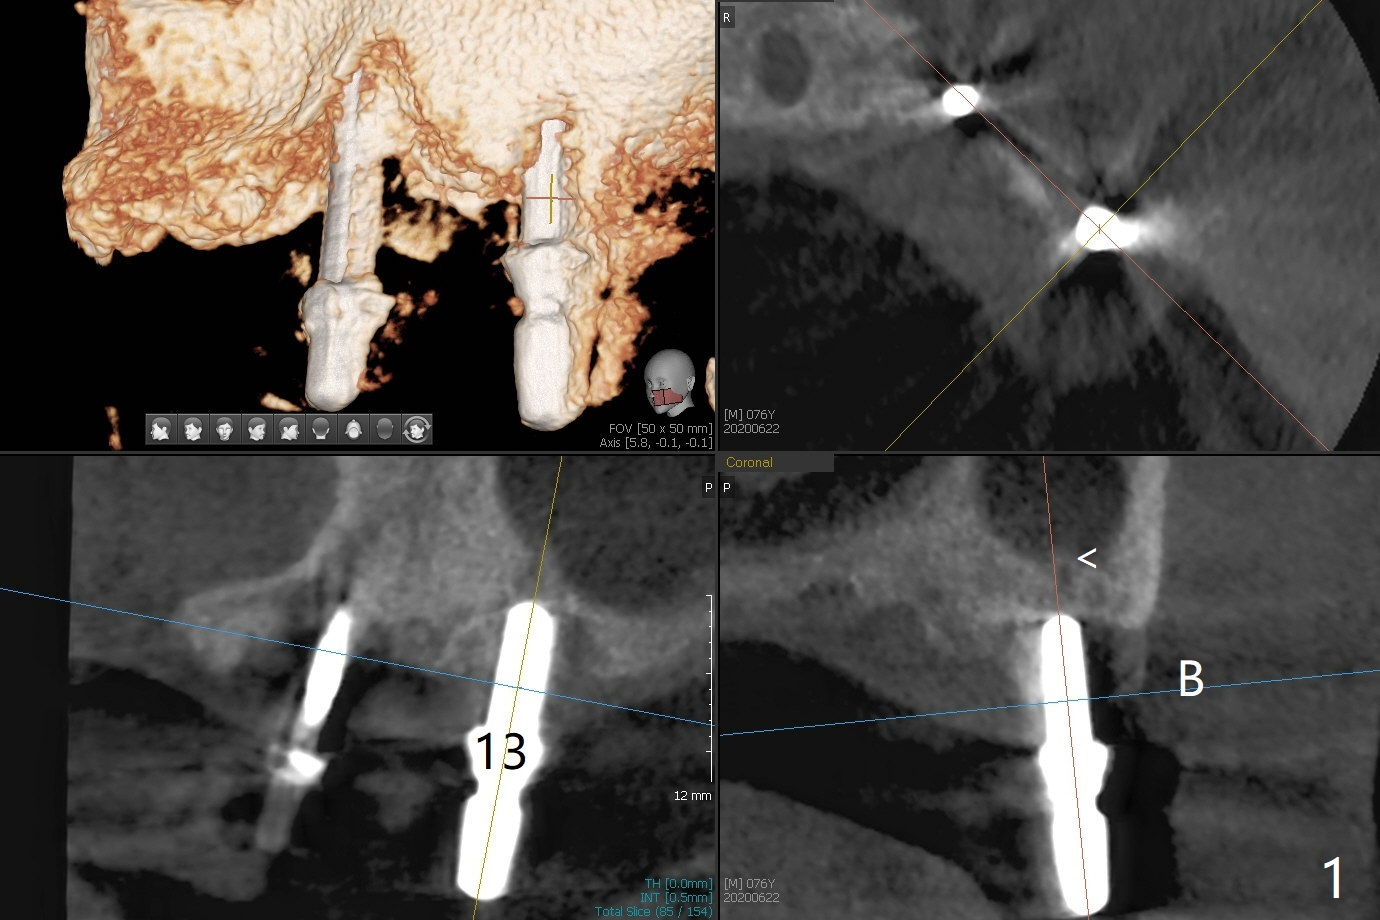

Osteotomy at #13 starts blindly (no incision or tissue punch) with bone expanders. After insertion of parallel pins, intraop CT shows that it is palatal with apparently buccal low bone density (Fig.1); the osteotomy for implant (Fig.2 green) should be shifted buccal and tilted mesial (red, parallel to #11) with incision. In contrast the position, trajectory and depth (Fig.3 <) of the initial osteotomy are acceptable at #11. The implant will be placed as it is (Fig.4). After taking a postop PA (Fig.5), the implant at #11 is placed a little deeper to make sure its slightly subcrestal placement (including distal incision at #11). Following placement of 3.5x4 and 3 mm ball abutments at #11 and 13, cortical allograft with PRF is placed around the implants, especially buccal (Fig.6,7 <). After suturing, the profile of the ball abutments is too low for RPD retention. Due to gravity other than bone density, the number of ball abutments for the maxilla should be more than for the mandible. Soft reline is done to the patient's satisfaction. The retention of the upper RPD after soft reline is satisfactory without pain 7 days postop (Fig.8). The implant at #13 is loose nearly 3 months postop (Fig.9 *: bone loss). The implant is removed while the ball abutment is untightened; the sinus floor is present. It appears that a longer and larger implant is necessary; a 4.5x10 mm dummy implant is unable to be seated deep or achieve primary stability (Fig.10). After sinus lift with 3 mm Bicon osteotome without bone graft, the dummy implant accomplishes the 2 tasks mentioned above (Fig.11). However there is no corresponding definitive implant in stock. Implant system needs to be changed; with a change in implant driver, the depth control is lost. The final implant is placed deep (Fig.12). With back up, stability is lessened; a healing screw is placed; with collagen plug, the wound is sutured (Fig.13). The wound heals 1 week postop (Fig.15). The RPD is soft relined. Retention from the ball abutment at #11 is apparently critical. The RPD and #11 implants (4 months postop) are stable, while the wound at #13 heals 1.5 months postop (Fig.15). There is space around the implant 5.5 months postop (Fig.16 *). The 5x10mm SM implant is found to be loose upon uncover and removed. After debridement, 5.3x8 mm SM and 5.5x9 mm IBS dummy implants are inserted without stability, while 6x9 mm definitive one with stability (Fig.17). Cortical allograft is placed in deficiency areas (*). The osteotomy has no roof (sinus floor), but the sinus membrane is intact. Small amount of bone graft (Fig.18 *) is placed before implantation. There appears to be bone around the new implant (Fig.19 (3D sagittal section) *).